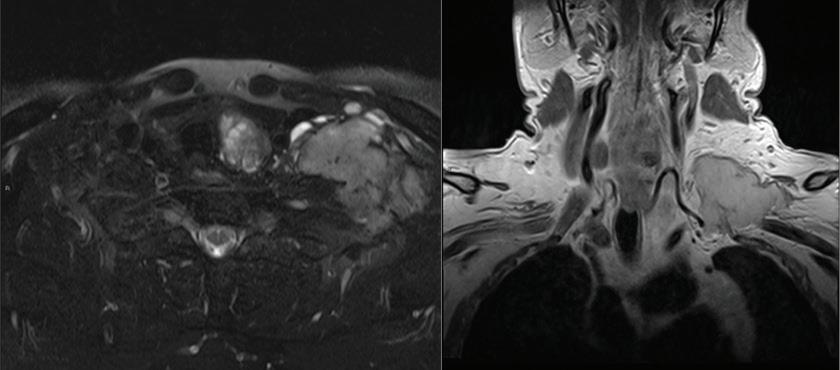

Huge primary leiomyosarcoma of the thyroid gland

Primary leiomyosarcoma (LMS) of the thyroid gland is a rare thyroid malignancy, accounting for only 0.014% of primary thyroid tumors.1 It has an aggressive clinical course with a low survival rate. Diagnosis of LMS is challenging as it has a pathologic resemblance to other thyroid tumors. Therefore, immunohistochemical staining is essential for diagnosis.

There are 26 previously reported cases of primary thyroid LMS.2,3 Of the 26 patients, 14 died within 6 months due to the disease; only 7 lived >1 year, and only 1 patient survived for >5 years.3

An 83-year-old woman who presented with aggravated dyspnea over a period of 1 month was admitted to our tertiary referral hospital. She had a history of Graves disease with a multinodular goiter involving the thyroid gland and had been receiving medical treatment with methimazole. On physical examination, a hard, protruding mass was noted in the anterior neck over the right thyroid cartilage. The cartilage was shifted toward the left side due to mass effect. Computed tomography (CT) with enhancement of the patient’s neck showed a huge (10 cm) mass in the right thyroid with luminal narrowing of the upper trachea due to mass effect (figure 1).

The patient underwent total thyroidectomy. Pathologic examination showed the mass to be positive for vimentin, cytokeratin, and actin, and negative for TTF-1, thyroglobulin, CD34, and EMA (figure 2). Therefore, the diagnosis of primary thyroid LMS was conclusive.

Considering the patient’s age and general condition, no other treatment was planned. At follow-up 12 months after surgery, the patient was still alive with no evidence of recurrence.

The etiology of primary LMS of the thyroid gland is not clear, although some studies have emphasized that the site of origin may be smooth muscles in blood vessels within the capsule of the thyroid.3 It has also been proposed that LMS may originate as a result of smooth-muscle metaplasia from a previously existing anaplastic carcinoma of the thyroid.4,5 There is also a reported case of an LMS of the thyroid associated

From the Department of Otolaryngology–Head and Neck Surgery, Research Institute for Clinical Medicine, Chonbuk National University, Chonbuk, Korea. Figure 1. A-C: Contrast-enhanced neck CT images show the 10-cm heterogeneous mass with rim calcification on the right thyroid gland. The trachea is deviated to the left. D: An excised surgical specimen shows a homogeneous and partially cystic change.

with Epstein–Barr virus in a child with congenital immunodeficiency.6

There are several treatment options for LMS. In many reported cases, thyroid lobectomy or total thyroidectomy with or without neck dissection has been the first choice for treatment. Although surgery is the most commonly accepted treatment for the disease, no treatment has shown effectiveness. However, it is difficult to make an exact diagnosis of LMS before surgery and to distinguish it from anaplastic thyroid cancer, especially the spindle-cell variant of anaplastic thyroid cancer.1,2